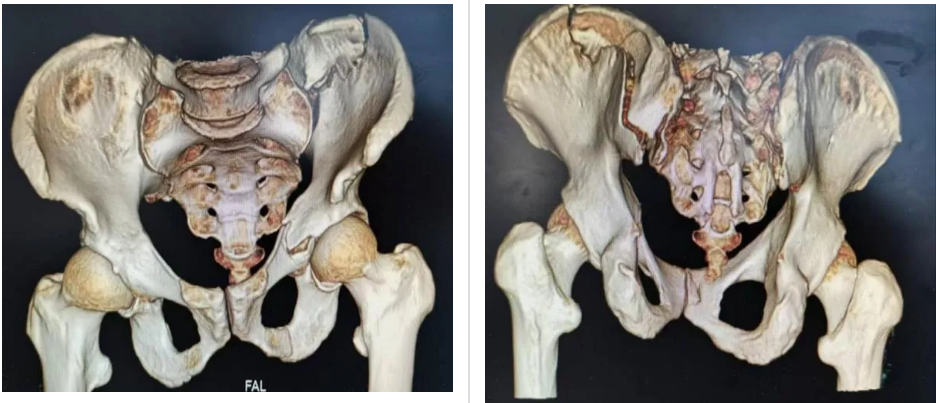

患者是一名高空墜落導(dǎo)致骨盆、髖臼骨折的老年男性。入院后完善術(shù)前檢查,結(jié)合骨盆三維CT掃描診斷為骨盆骨折合并左側(cè)髖臼骨折及骶髂關(guān)節(jié)脫位(分型為TileC1.3)。由于骨盆內(nèi)分布許多重要臟器以及血管神經(jīng),對(duì)于手術(shù)操作精準(zhǔn)度要求極高,否則容易傷及周圍神經(jīng)血管或盆腔臟器。為最大程度減少手術(shù)創(chuàng)傷及出血,骨關(guān)節(jié)外科冷明昊主任經(jīng)過充分考慮,決定在新型“HoloSight智能可視化系統(tǒng)”機(jī)器人的輔助下,為患者實(shí)施微創(chuàng)手術(shù)。

術(shù)中,在醫(yī)院手術(shù)室的大力支持下,主刀醫(yī)生冷明昊主任首先將定位追蹤器安置在患者髂棘合適位置上,再結(jié)合CT透視所得將患者骨盆影像資料導(dǎo)入手術(shù)機(jī)器人中,通過機(jī)器人自動(dòng)化算法將影像圖片與骨盆實(shí)體情況進(jìn)行精準(zhǔn)配對(duì),并在顯示器上規(guī)劃好骶髂螺釘、前柱螺釘位置、長度以及角度,隨后準(zhǔn)確無誤地將骶髂螺釘、前柱螺釘植入患者體內(nèi)。手術(shù)全程通過機(jī)器人監(jiān)視下調(diào)整角度,快速定位、精準(zhǔn)植入、切口僅用1cm,術(shù)中出血量約10ml,手術(shù)安全順利結(jié)束。術(shù)后,患者恢復(fù)良好,目前可在床上自行翻身、端坐等活動(dòng)。